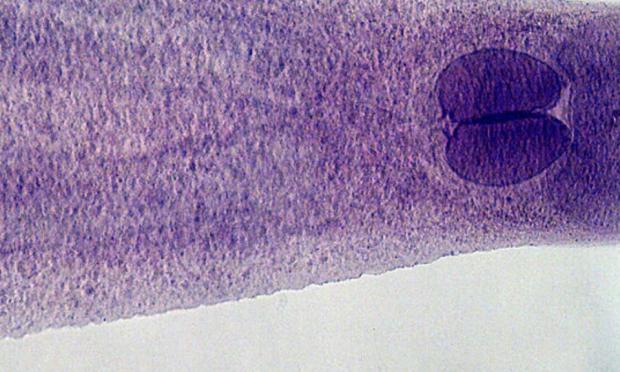

Μια επακόλουθη εξέταση αποκάλυψε ότι η τρύπα φιλοξενούσε αμέτρητα αυγά «σε σχήμα βολβού, κελύφους» που ανήκουν σε ένα παράσιτο που βρίσκεται στα ωμά θαλασσινά και ονομάζεται κλωνόρχις ο κινεζικός (Clonorchis sinensis).